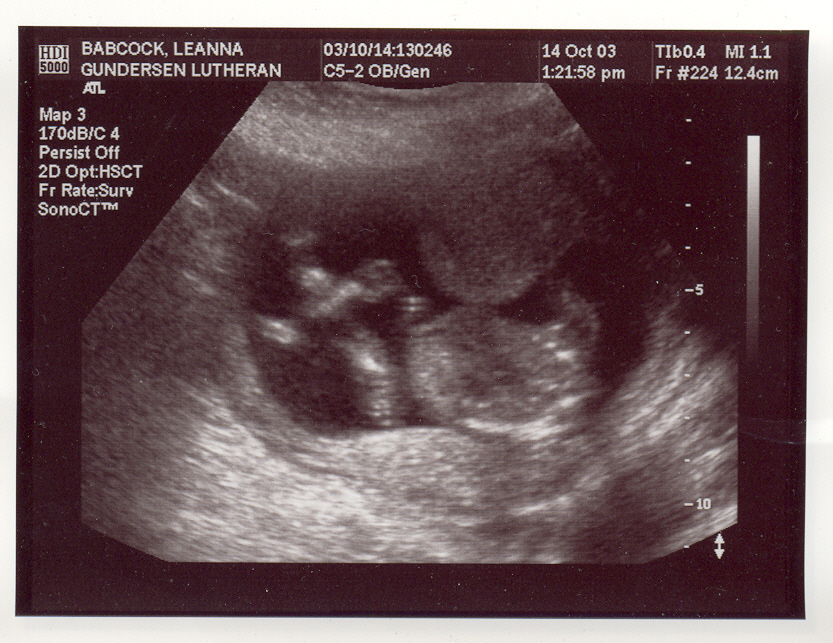

This is my new baby page. I am due at the end of March/start of April, 2004. Here are my first ultrasound pix. They may take a few minutes to load, so be patient. These ultrasound pix were taken Oct. 14th, 2003. We were unable to find out the sex of the baby because it was too early in my pregnancy and also the baby's umbilical cord was between it's legs, and whenever we tried to see what was down there that was blocking our view, and also the baby would put it's hands in the way. I go in for another ultrasound on Nov. 11th. I will post more pix up after then. The baby seems to be healthy at this point and Aidan and I are very excited and preparing for our first child with joy in our hearts! :)